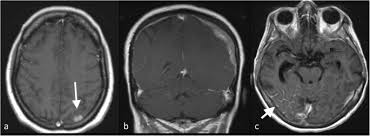

Brain Metastases From Breast Cancer Radiology Case Radiopaedia Org from prod-images-static.radiopaedia.org A ct scan (also called a cat scan or computed tomography scan) can help doctors find cancer and show things like a tumor's shape and size. Ct scans are most often an outpatient procedure. Nevertheless one ct scan cannot cause cancer not even a a few more done in a short time. Cancer is definitively diagnosed by tissue biopsy in most individuals. However, the risk from any one scan is small. In some cases, physicians use all three imaging techniques. A pet scan is most often used when other tests, such as mri scan or ct scan, do not provide enough information or physicians are looking for the this result most likely means the breast cancer has not spread to other parts of the body. Pet scans are not used to screen women for breast cancer.